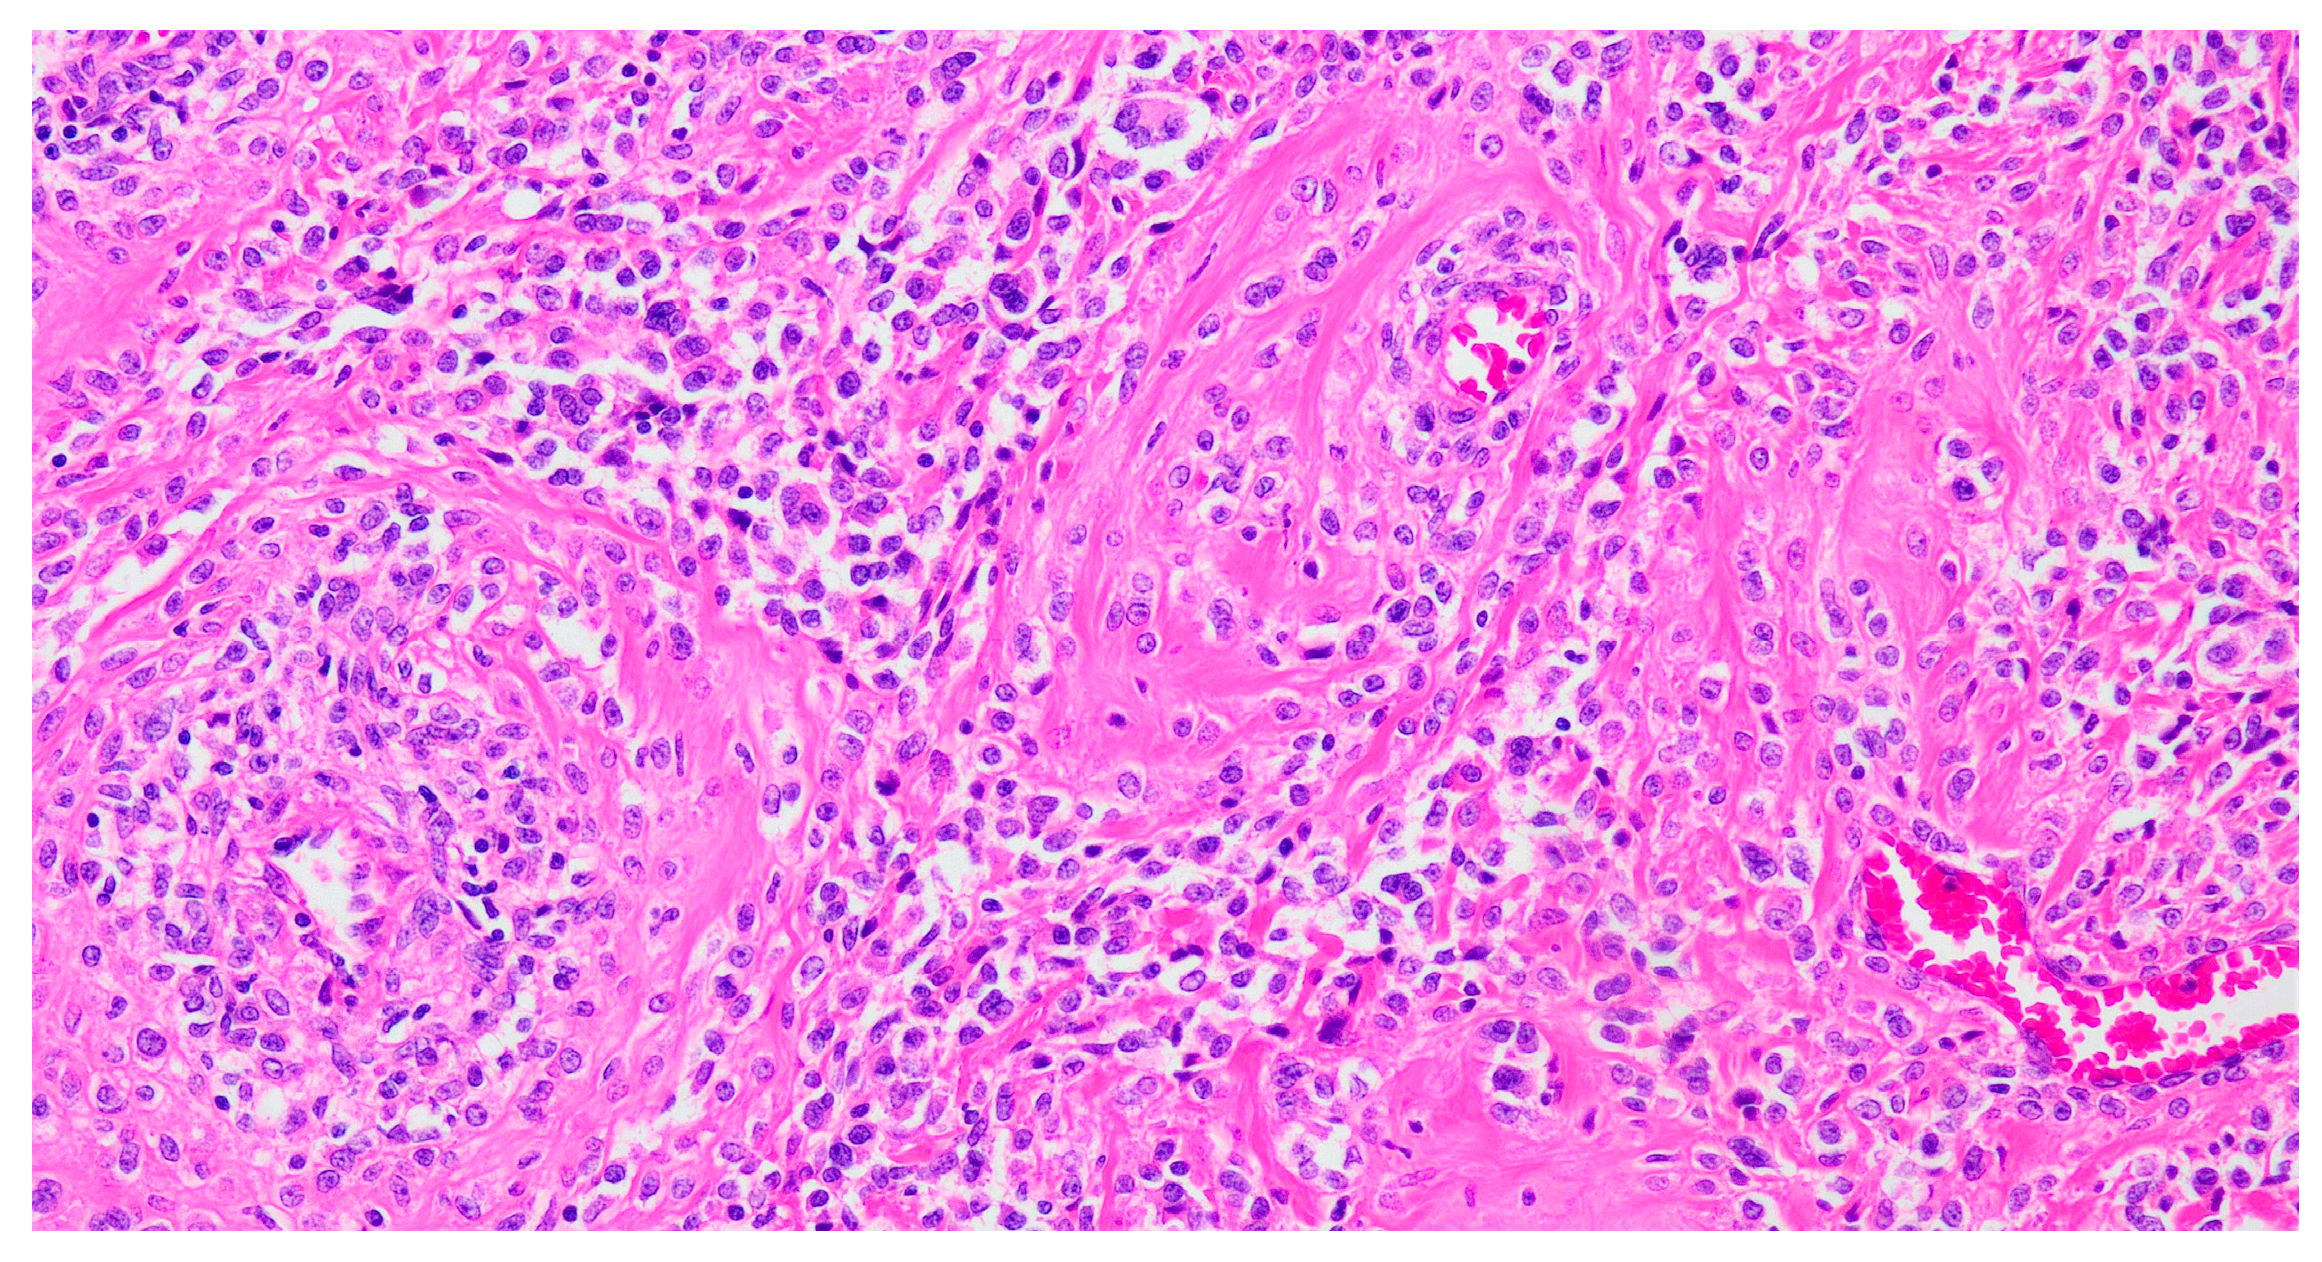

Histologically, PEComas are composed of epithelioid cells and, less frequently, spindle cells. Epithelioid cells exhibit clear to eosinophilic granular cytoplasm and are typically arranged in dyscohesive nests surrounded by delicate, thin-walled blood vessels and/or in solid sheets (Figure 2). In contrast, spindle cells often form fascicles. Additional features may include perivascular distribution, multinucleated cells, lipid-rich or rhabdoid cytoplasm, and stromal hyalinization. Tumors may display expansile, permeative, or infiltrative growth patterns. Both cell types can show variable degrees of cytological atypia and mitotic activity, and melanin pigment may also be present [24].

Figure 2.

Hematoxylin–eosin-stained section from a uterine PEComa. Epithelioid cells with clear to eosinophilic cytoplasm in a radial/perivascular distribution, with stromal hyalinization (20× magnification).